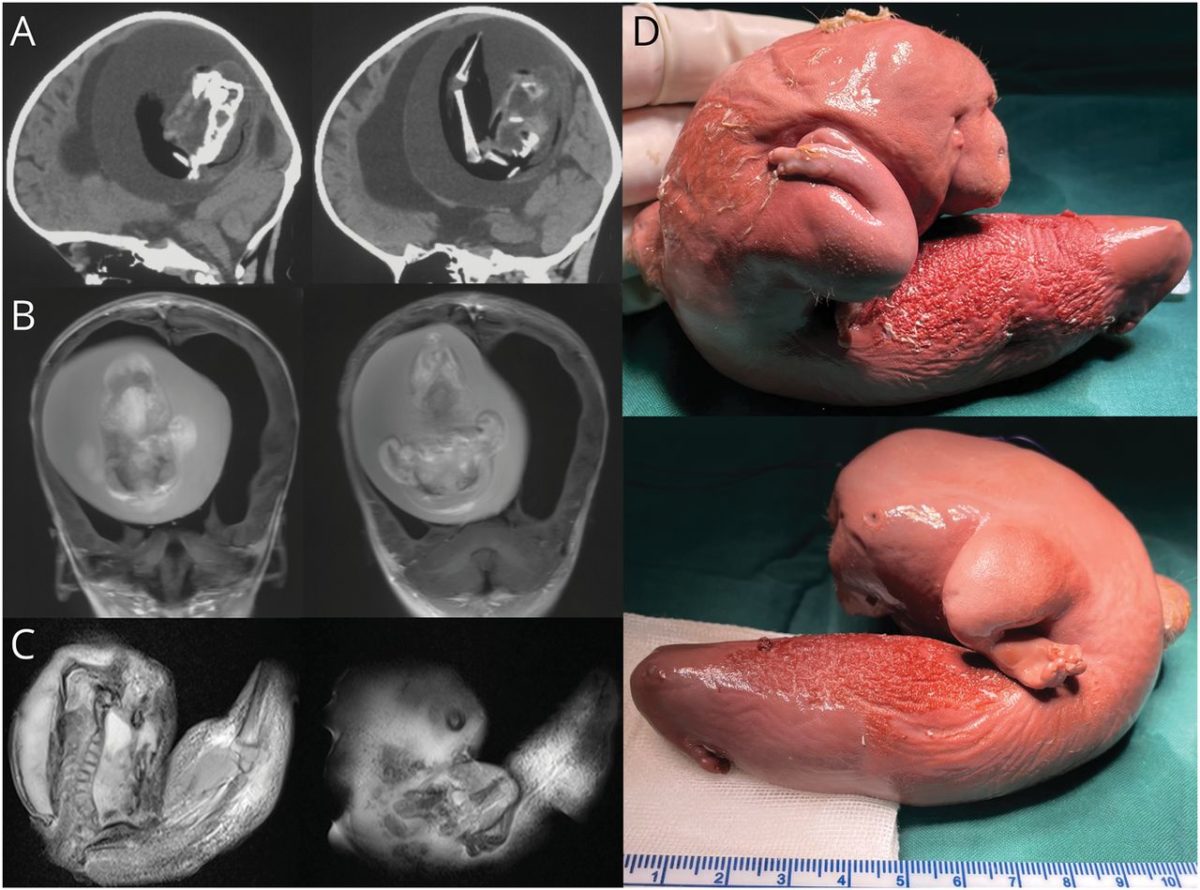

Η μικροσκοπική “εμβρυϊκή μάζα” φαίνεται να έχει αναπτύξει άνω άκρα και ακόμη και προεξοχές σαν δάχτυλα.

Οι γιατροί στο Πανεπιστήμιο Fudan στη Σαγκάη εξήγησαν ότι το παιδί παρουσίασε διευρυμένο κεφάλι και προβλήματα με τις κινητικές της δεξιότητες. Οι αξονικές τομογραφίες του κεφαλιού της έδειξαν ότι ο εγκέφαλός της ήταν συμπιεσμένος και ότι υπήρχε συσσώρευση υγρού που προκλήθηκε από μια σημαντικού μεγέθους μάζα.

Οι λεπτομέρειες στην σχετική δημοσίευση δεν είναι κατατοπιστικές, αλλά οι συγγραφείς περιγράφουν ότι πραγματοποιήθηκε χειρουργική αφαίρεση, που αποκάλυψε μια σπάνια περίπτωση “ενδοκοιλιακού εμβρύου μέσα σε έμβρυο”!

Με άλλα λόγια, το έμβρυο του αγέννητου διδύμου ήταν μέσα στο κρανίο της… αδελφής του.

Οι συντάκτες της έκθεσης προσθέτουν: “Τα συνδεδεμένα μέρη αναπτύσσονται στον πρόσθιο εγκέφαλο του εμβρύου-ξενιστή και περιβάλλουν το άλλο έμβρυο κατά τη διάρκεια της αναδίπλωσης της νευρικής πλάκας”.

Ωστόσο, υπήρξαν και άλλες παρόμοιες περιπτώσεις όπου τα παιδιά ανάρρωσαν καλά. Σε μια μελέτη, που δημοσιεύθηκε το 1982, επιστήμονες στο Νοσοκομείο του Λονδίνου ανέφεραν ένα έμβρυο μήκους 14 εκατοστών μέσα σε ένα παιδί ηλικίας 1,5 μήνα που παρουσίαζε μεγέθυνση του κεφαλιού. Το έμβρυο που αφαιρέθηκε είχε επίσης αξιοσημείωτα χαρακτηριστικά όπως αναπτυσσόμενα άκρα, κεφάλι και σώμα. Μετά το χειρουργείο, το παιδί λέγεται ότι είχε καλή ανάρρωση.